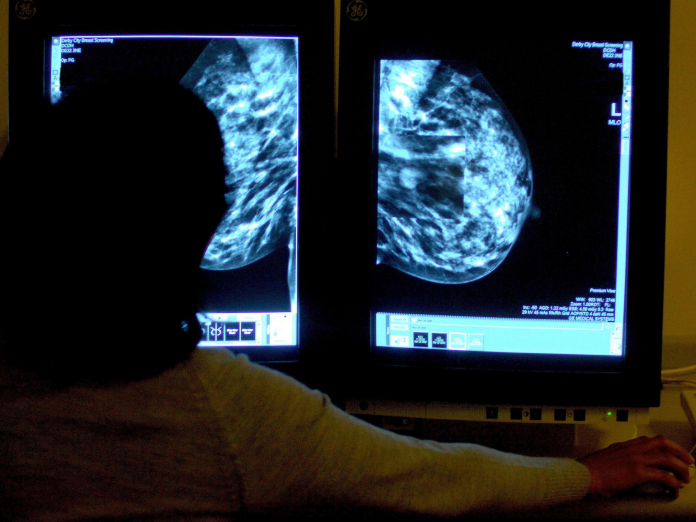

According to a new study published last week in the Lancet, women who undergo hormonal therapy during menopause are more likely to develop breast cancer and the risk remains high for over a decade after stopping the treatment.

Post-menopausal women are often prescribed hormonal therapy because they tend to secrete less hormone after attaining the climacteric age. Hormonal therapy is usually prescribed in the form of a tablet, a patch, a gel, or an injection. For most women, hormone therapy helps to alleviate menopausal symptoms, including osteoporosis.

The study found that the risk of breast cancer is more if women use menopausal hormonal therapy for a longer period. The researchers found that women had a relatively lower risk who were no longer using the therapy; however, the risk remained high for over a decade after stopping the therapy.

The research also found that women who undergo combination drug therapy were at greater risk of developing breast cancer than those who underwent only estrogen therapy.